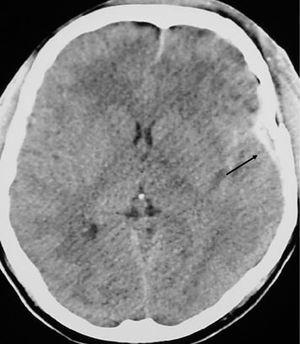

Focalidad neurológica en el paciente anciano

García García, López-Tarruella Cobo, Puche Paniagua, Cubo Romano, Ruiz-Yagüe

Rev Clin Esp 2005;205:625-6